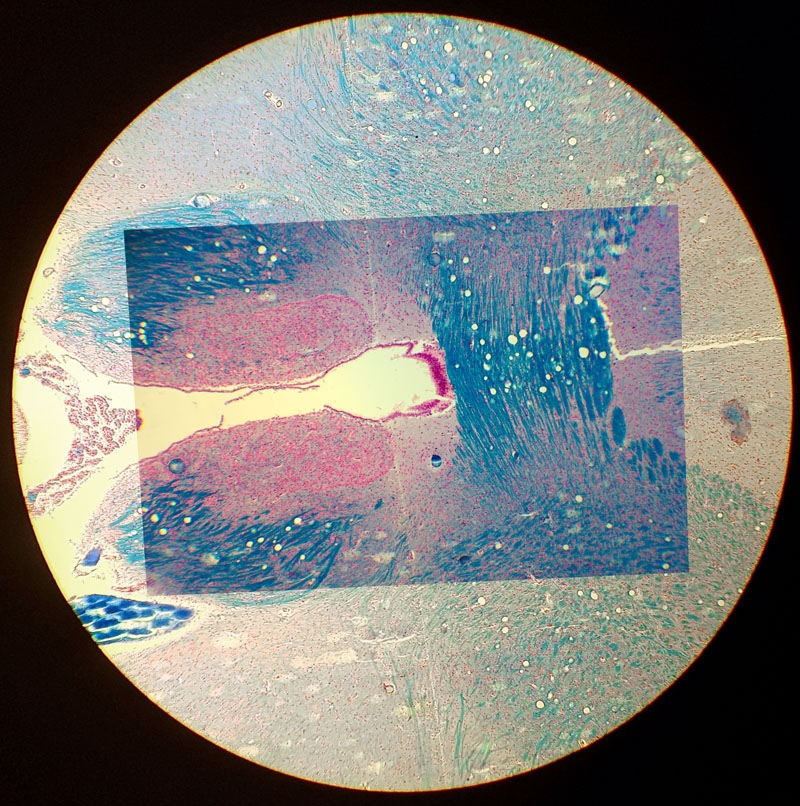

Hallo Ronald, auf dem ersten Bild sieht man ein Foto, dass mit dem Samsung S7 durch ein Periplan GF 10x aufgenommen wurde. Von einem digitalen Zoom habe ich abgesehen. Schade, dass Smartphones keinen 2x optischen Zoom haben. Damit wäre viel gewonnen.

Das zweite Foto enstand mit einer Pentax K-3 über einem Zeiss Kpl W 10x Okular am LEitz Ortholux II. Die Kombination ergibt nur in der Mitte ein gutes Foto; zum Rand hin bricht es ein. Aber es zeigt mehr vom Bild als mein Periplan GF 12,5x MF Okular vor der Kamera, welches das Bild stärker beschneidet.

Ich hätte nichts dagegen, mit der DSLR den vollen oder leicht angeschnittenen Kreis aufzunehmen, weil die Auflösung der Sensoren groß genug für die nachträgliche Auswahl eines Ausschnittes ist.

Tom

Foto mit dem Smartphone Samsung S7

Foto der DSLR und dem Zeiss Kpl W 10x. Das Okular passt nicht zu den Leitz Objektiven, Das sieht man vor allem in Richtung Bildecken an den starken Farbsäumen. Mit meinem Leitz PEriplan GF 12,5 MF ist das Bild besser, aber der Ausschnitt noch kleiner.

Vergleich beider Bilder. Die DSLR nimmt einen zu kleinen Bereich auf.